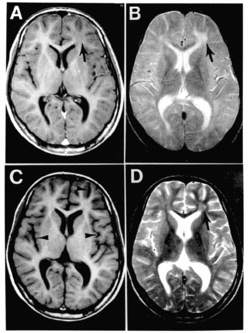

![]() Obraz MRI mózgu pacjenta z SSPE | |